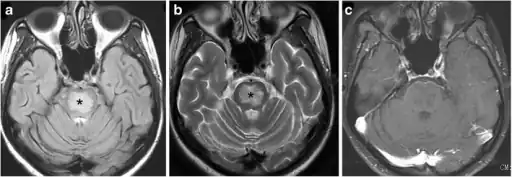

Treatment

It is crucial to first assess the stability of the patient. If there are any signs of shock such as tachycardia or hypotension, these must be treated immediately with IV saline infusion.[4][21] Once the patient is stable, it is important to identify the underlying cause of hypernatremia as that may affect the treatment plan.[4][21] The final step in treatment is to calculate the patients free water deficit, and to replace it at a steady rate using a combination of oral or IV fluids.[4][21] The rate of replacement of fluids varies depending on how long the patient has been hypernatremic. Lowering the sodium level too quickly can cause cerebral edema.[21]